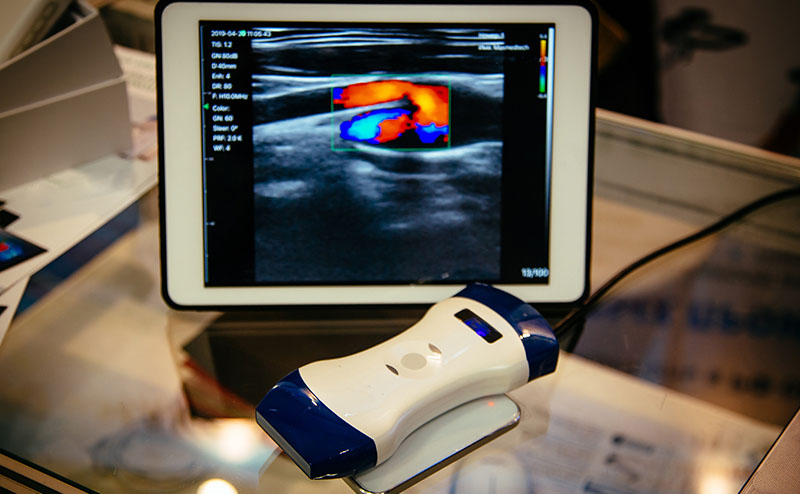

The integration of handheld Point-of-Care Ultrasound (POCUS) devices has quickly become a core component of undergraduate medical education (UME). A recent panel of expert ultrasound educators, hosted by the ACEP Emergency Ultrasound Medical Student Subcommittee, shared critical insights on scaling programs, managing resources, and overcoming administrative barriers.